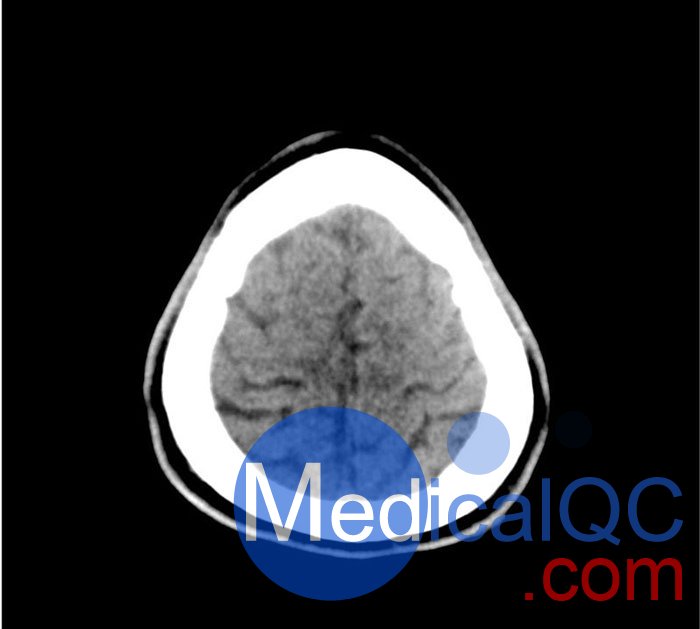

50-01头部CT模体,50-01脑中风头部模体,50-01脑出血头部模体模拟了具有中风和出血模式的头部。它覆盖枕骨大孔的顶点。

卒中模式包括早期梗死的体征(大脑中动脉高密度、基底神经节消失)、急性和亚急性分水岭梗死以及不同年龄的腔隙性梗死。

出血模式包括蛛网膜下腔出血、不同年龄的硬膜下出血、脑室内出血和脑出血。

该模型可用于 CT(包括 CBCT)以评估和优化成像性能和 AI 支持的诊断。它也适用于培训目的。

该模型提供了对常见大脑病理、软组织和骨组织的详细而逼真的模拟。空气空隙填充有约-160HU的纤维素-聚合物复合材料。

高密度大脑中动脉 (MCA) 和左侧基底神经节消失

中/后 (MCA/PCA) 和大脑前/中动脉 (ACA/MCA) 区域的分水岭梗死

8 个不同年龄的腔隙性梗死

蛛网膜下腔出血(2个地区)

不同年龄的硬膜下出血(3个地区)

脑室内出血(左侧脑室)

脑出血(2 个丘脑,6 个皮质下)

50-01头部CT模体,50-01脑中风头部模体,50-01脑出血头部模体影像效果图: